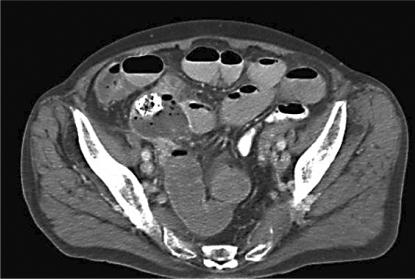

Covered self-expanding metallic stents are commonly employed to relieve malignant oesophageal obstruction. We report a case of a patient with oesophageal cancer treated by stent insertion and curative chemoradiotherapy with subsequent stent migration to the stomach. The stent fractured with the distal fragment migrating as far as the terminal ileum where it caused perforation of the bowel.

覆膜自膨式金属支架常用于缓解恶性食管梗阻。我们报告一例食管癌患者,接受了支架置入及根治性放化疗,随后支架迁移至胃内。支架发生断裂,远端碎片迁移至回肠末端,导致肠穿孔。